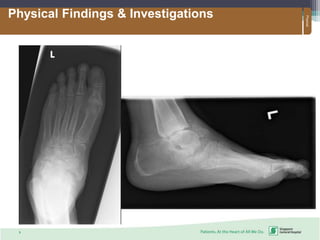

Physical Findings & Investigations

Presentation:

Vary from mild swelling and no deformity to moderate

deformity with significant swelling

Always presents with signs of inflammation: warmth, joint

effusion, erythema, bone resorption

Pain occurs in > 75% of patients

Instability and loss of joint function; “bags of loose bones”